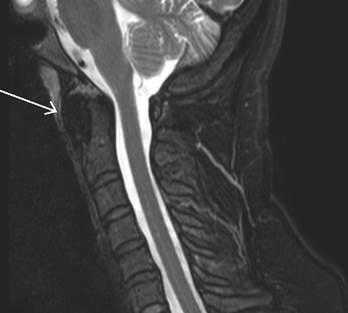

На мр-томограммах выявлялась расщелина (незаращение) передней дужки атланта, определялись особенности анатомического строения и особенности контуров передней дужки атланта в каждой из стандартных проекций (рис. 2).

Рис. 2. Коронарный и сагиттальный срезы Т2ВИ (стрелкой указаны поверхности расщепленной передней дужки)

Рис. 3. Сагиттальные томограмммы Т1 и Т2ВИ (красный контур сагиттальной плоскости сечения расщепленной передней дужки атланта)